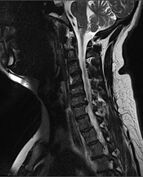

Cervical Spine MRI (T2W).jpg

MRI of a fractured and dislocated cervical vertebra (C4) in the neck that is compressing the spinal cord

X-rays (left) are more available, but can miss details like herniated disks that MRIs can show (right).[88]

A radiographic evaluation using an X-ray, CT scan, or MRI can determine if there is damage to the spinal column and where it is located.[9] X-rays are commonly available[88] and can detect instability or misalignment of the spinal column, but do not give very detailed images and can miss injuries to the spinal cord or displacement of ligaments or disks that do not have accompanying spinal column damage.[9] Thus when X-ray findings are normal but SCI is still suspected due to pain or SCI symptoms, CT or MRI scans are used.[88] CT gives greater detail than X-rays, but exposes the patient to more radiation,[90] and it still does not give images of the spinal cord or ligaments; MRI shows body structures in the greatest detail.[9] Thus it is the standard for anyone who has neurological deficits found in SCI or is thought to have an unstable spinal column injury.[91]